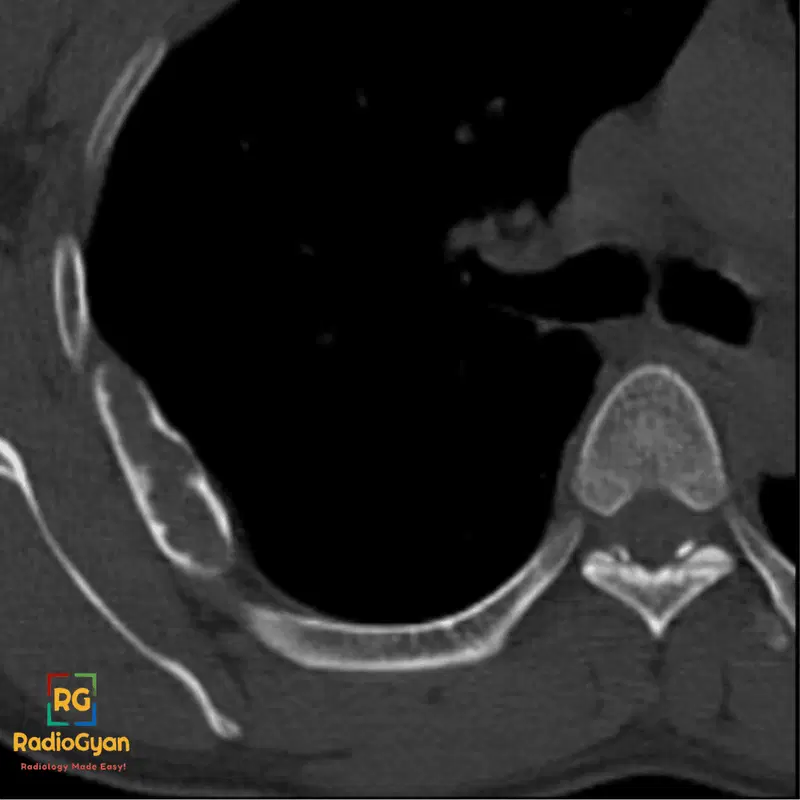

Axial CT image of the chest demonstrating fibrous dysplasia of the rib

CT image showing a bone lesion, consistent with fibrous dysplasia, affecting a rib.

• CT: Intramedullary expansile lesion with ground-glass opacity, cortical thinning or endosteal scalloping, well-defined margins, no soft-tissue mass, may show expansion and possible fusiform rib enlargement